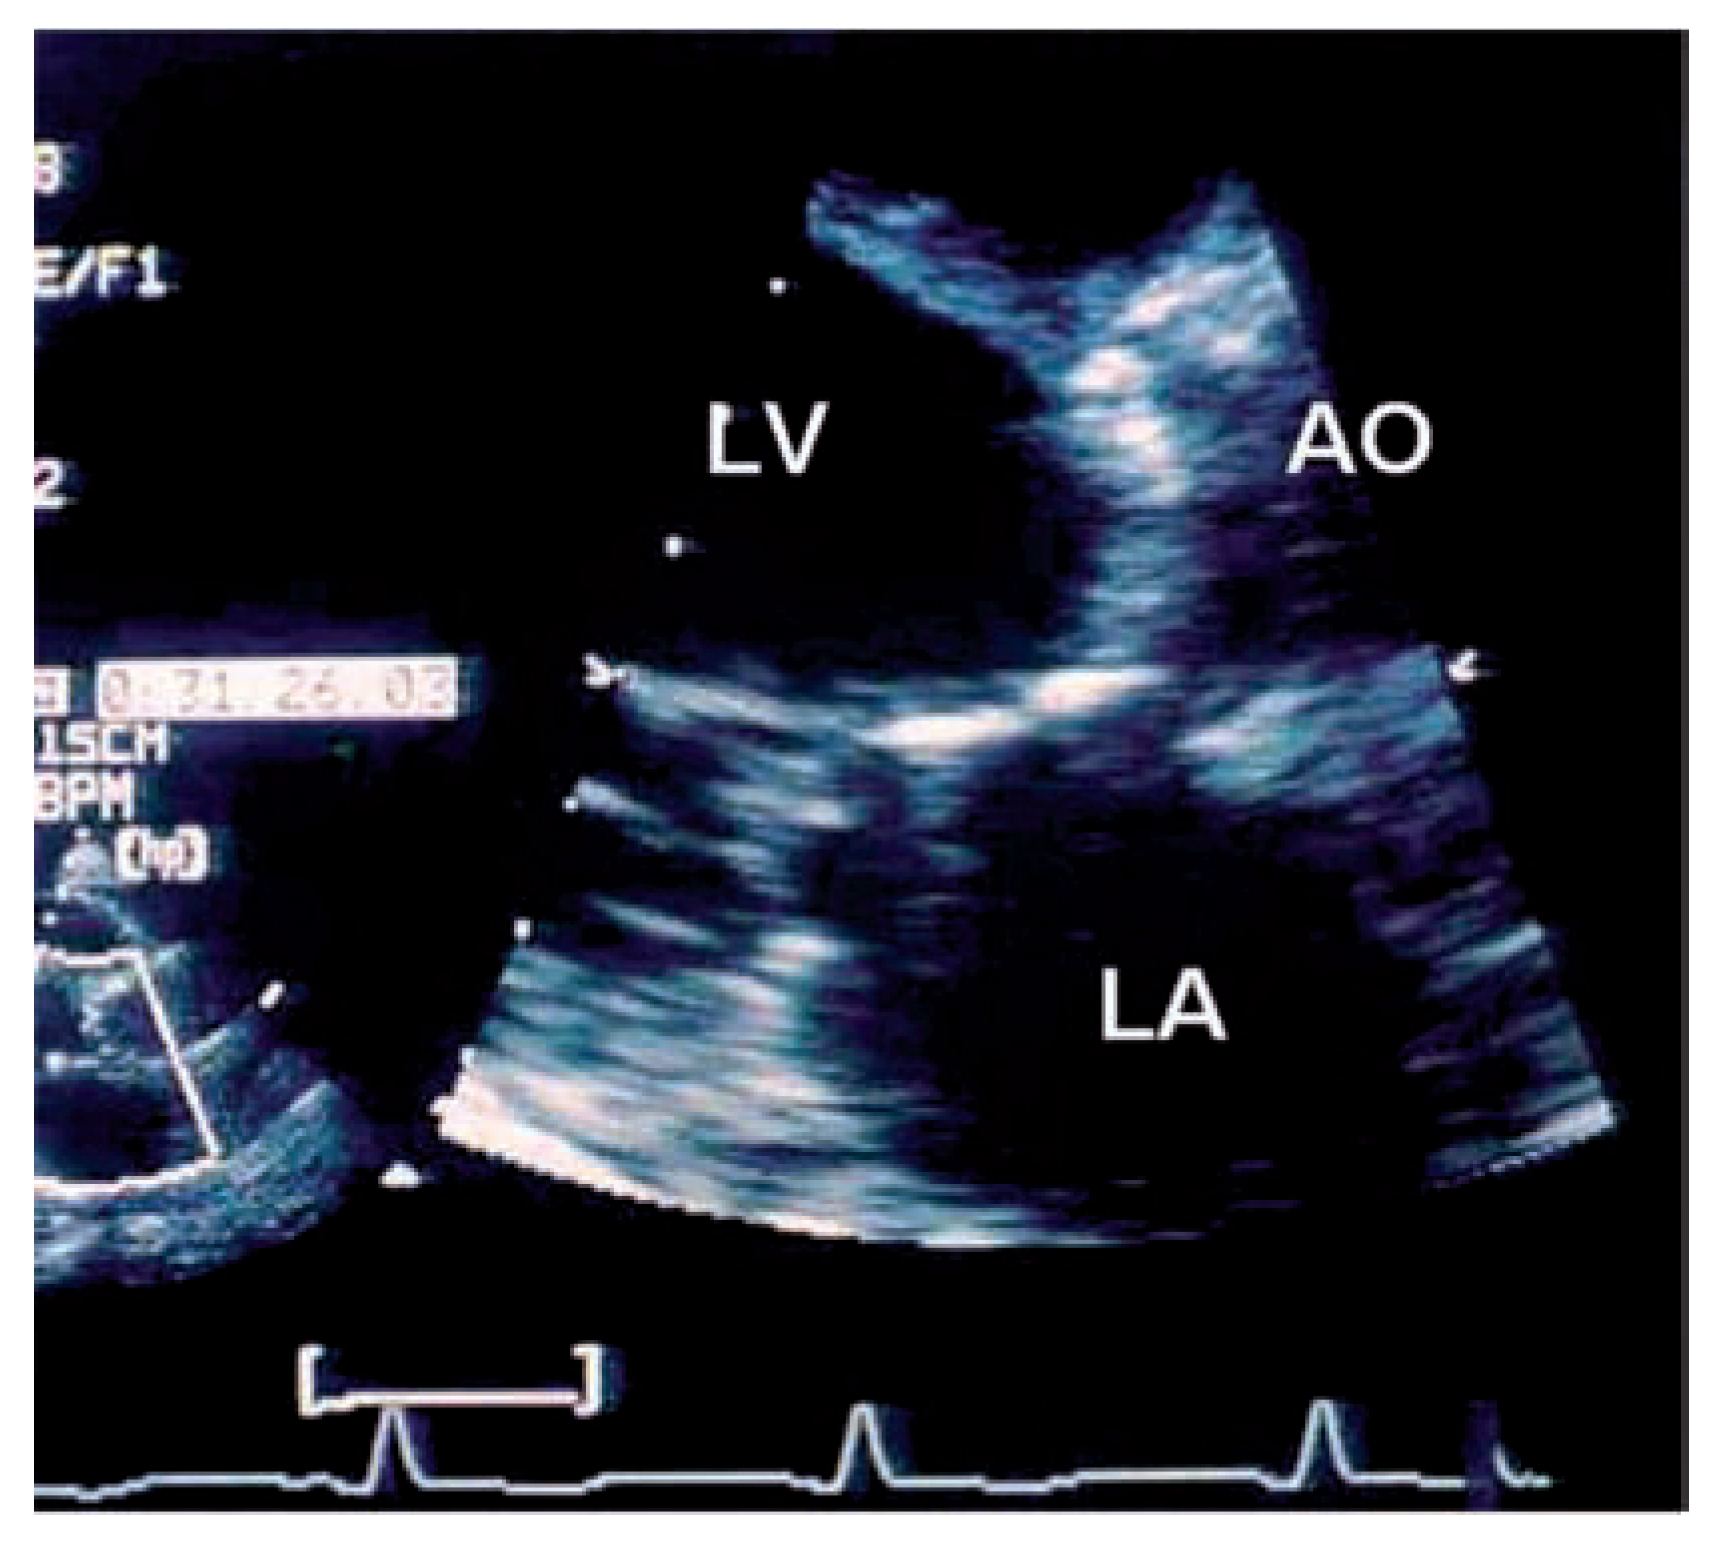

Echocardiographic findings

|